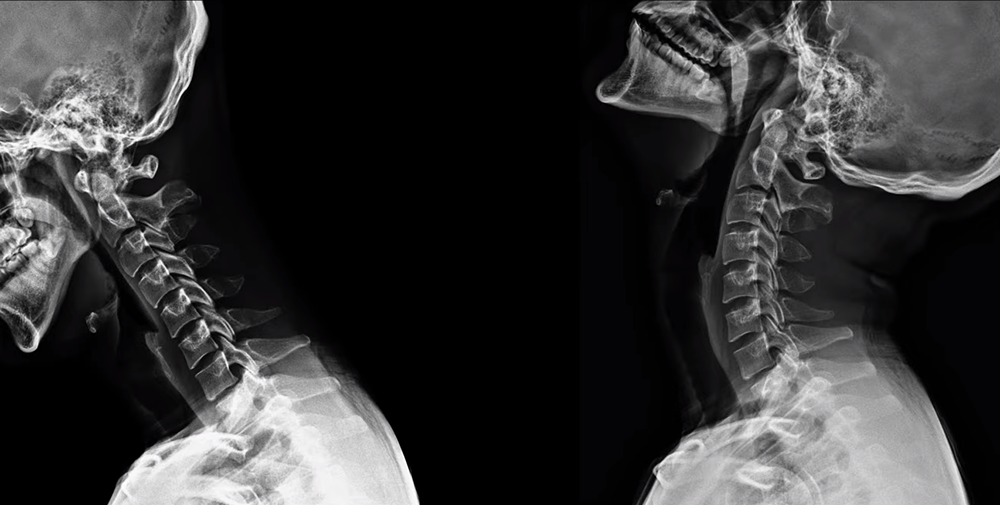

위 X-ray를 보면 정상적인 C자 커브를 가진 사람도 고개를 숙이면 일자목이 만들어지듯이, 거북목인 사람도 목을 뒤로 쭉 젖히면 순간적으로 C자 커브가 만들어질 수 있습니다. 그래서 거북목, 일자목 환자는 목을 뒤로 젖히는 운동을 지속적으로 해줘야 하는 것인데요. 이게 바로 맥켄지 운동입니다.